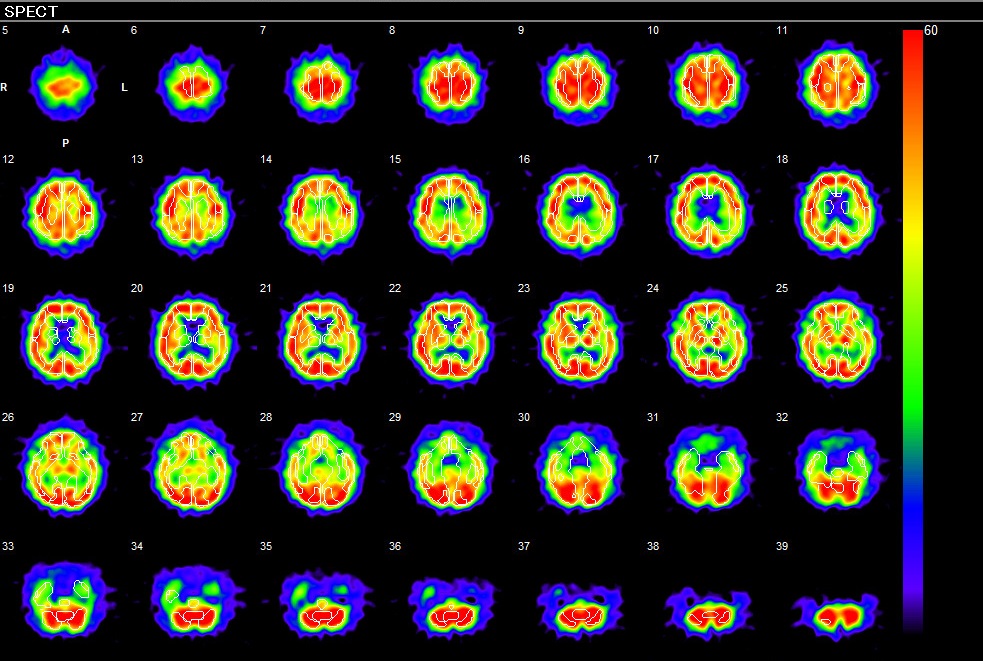

核医学検査室

核医学では認知症診療の一つとして脳血流SPECTを施行しています。脳血流SPECTでは脳血流が低下している部位を調べることにより認知症の早期診断や4大原因であるアルツハイマー型認知症やレビー小体型認知症、血管性認知症、レビー小体型認知症、前頭側頭型認知症などを鑑別することが可能です。 かかりつけ医や認知症サポート医の皆様の認知症治療やケアに有意義となる画像を提供しています。

アルツハイマー型認知症:後部帯状回・楔前部・頭頂葉の血流低下を認める